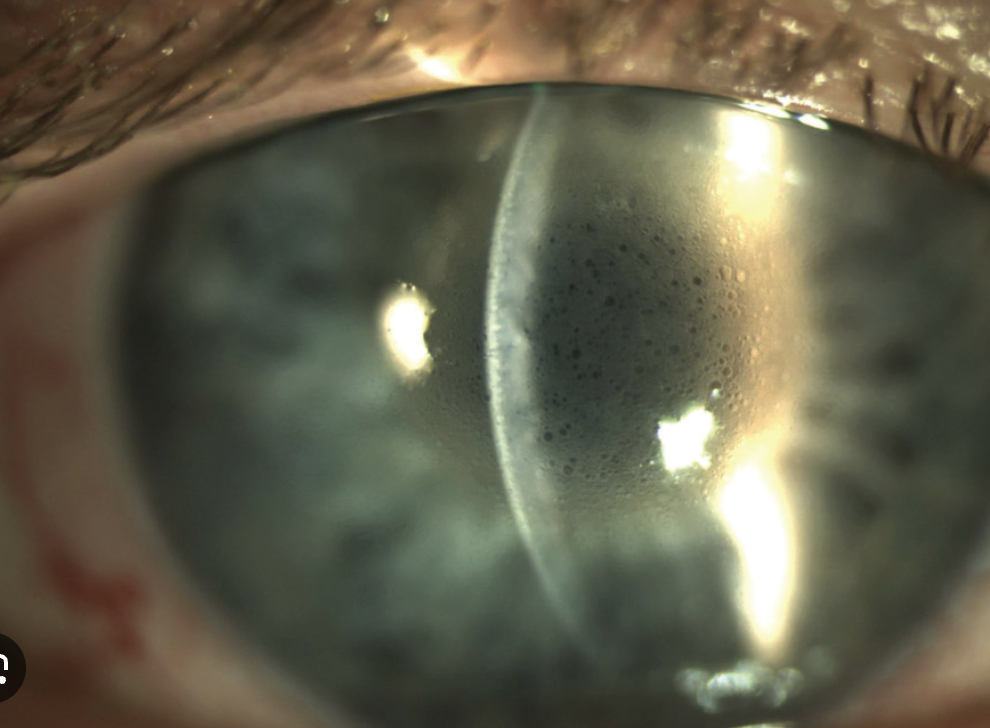

Q

Distrofia de fuchs

A

• Acomete a descemet

• cursa com densidade diminuída das células endoteliais e

edema corneano pela descompensação endotelial e hidratação estromal.

• Guttata